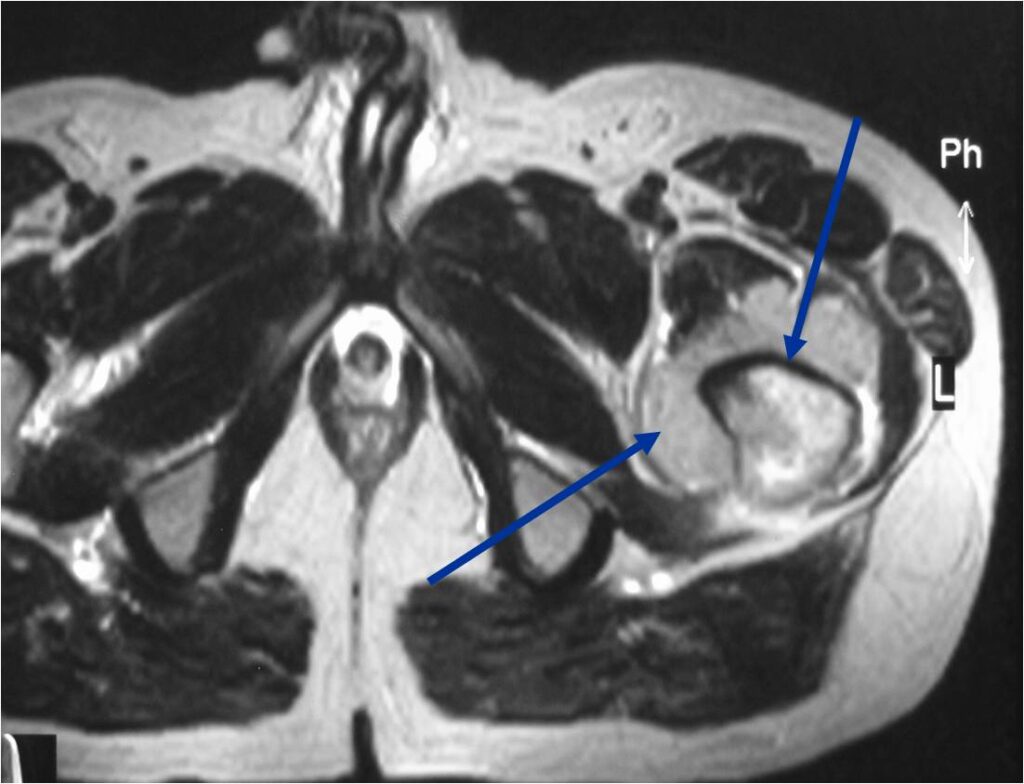

- Soft tissue mass— by CT (80%); by MRI (100%)

T2 Weighted MRI

TI Weighted MRI